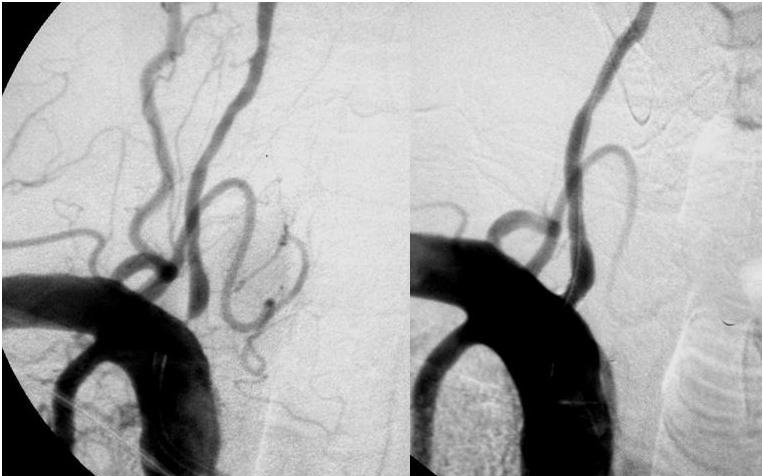

Stents en las arterias vertebrales: se precisan más estudios

09 octubre 2017

En pacientes con estenosis sintomáticas en el territorio vertebral el tratamiento con stents no fue superior al manejo médico óptimo. Neurology, 19 de septiembre de 2017